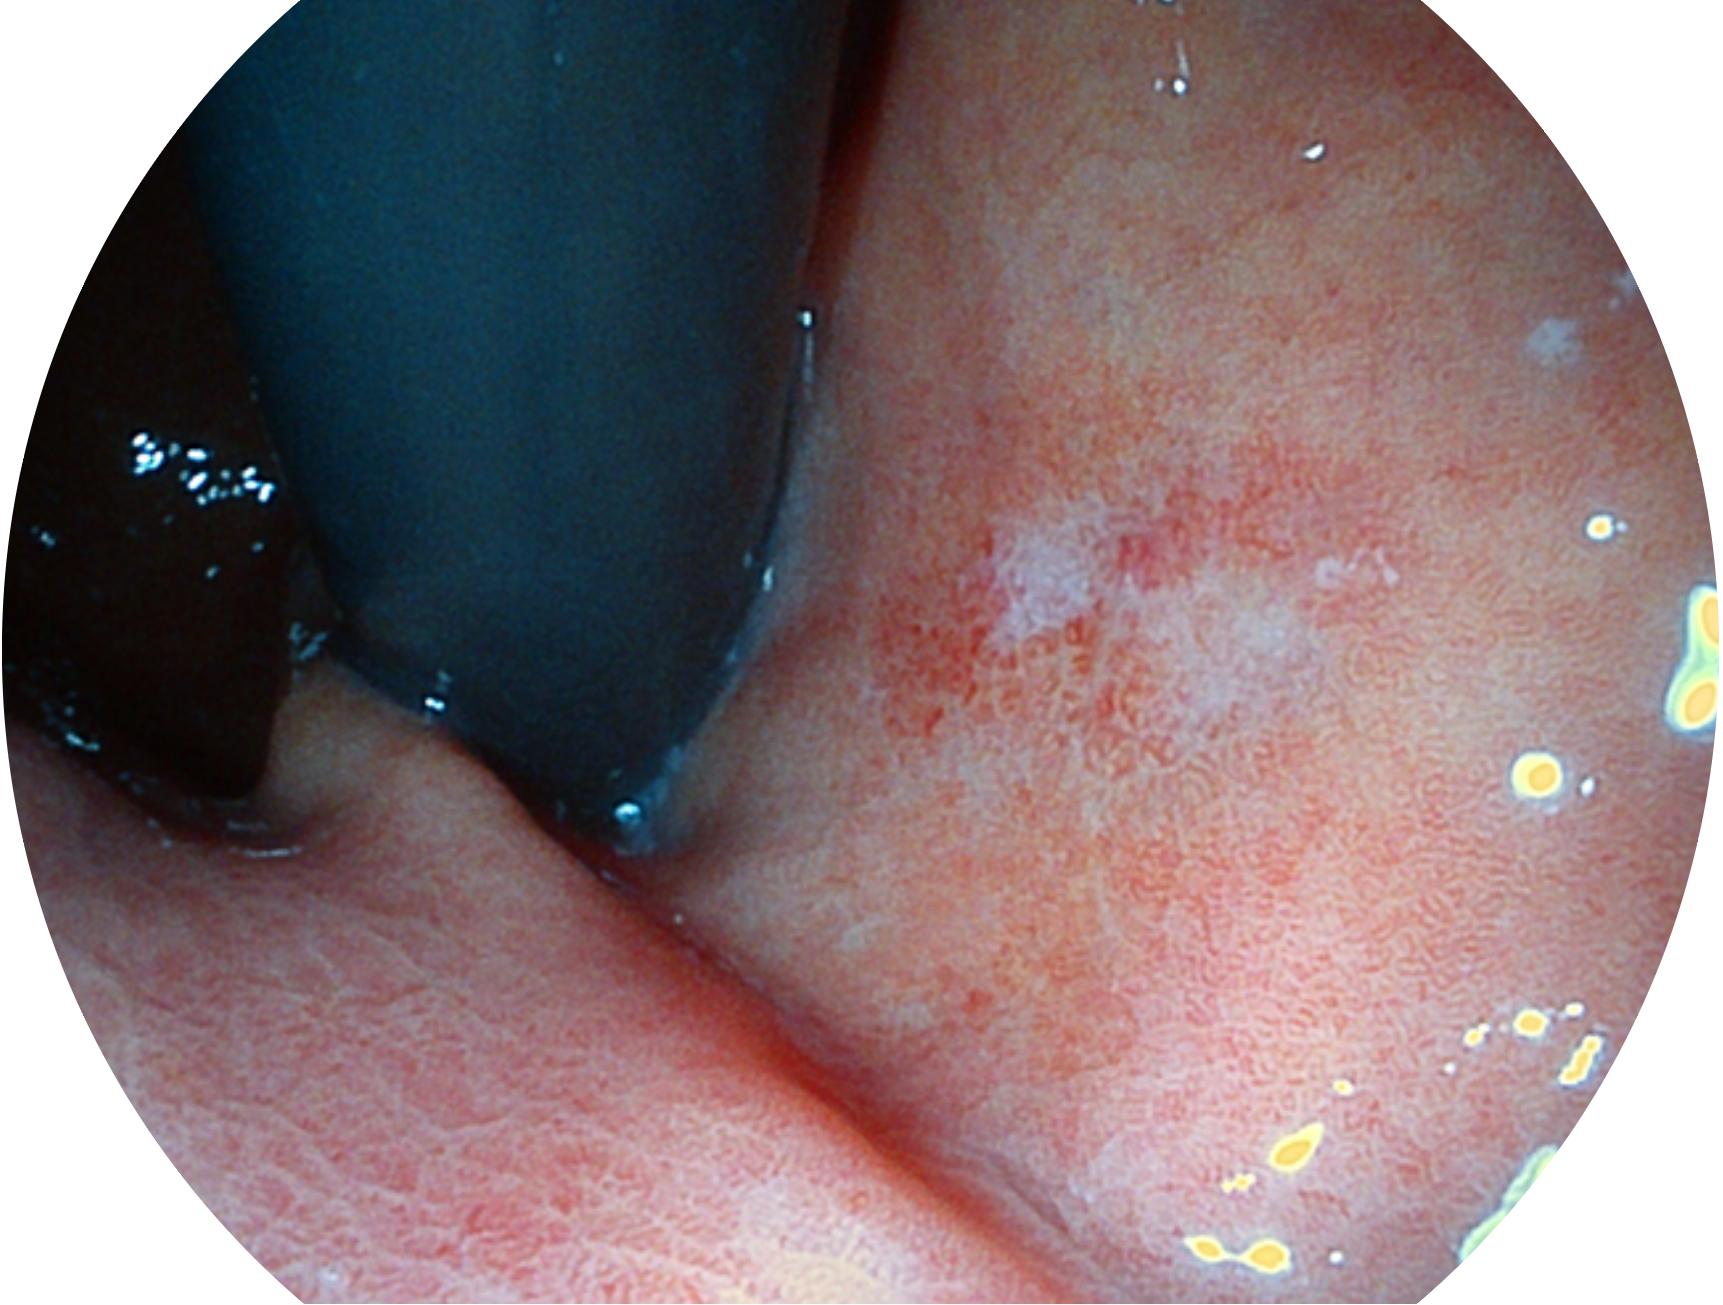

• 白光圖像 SFI圖像